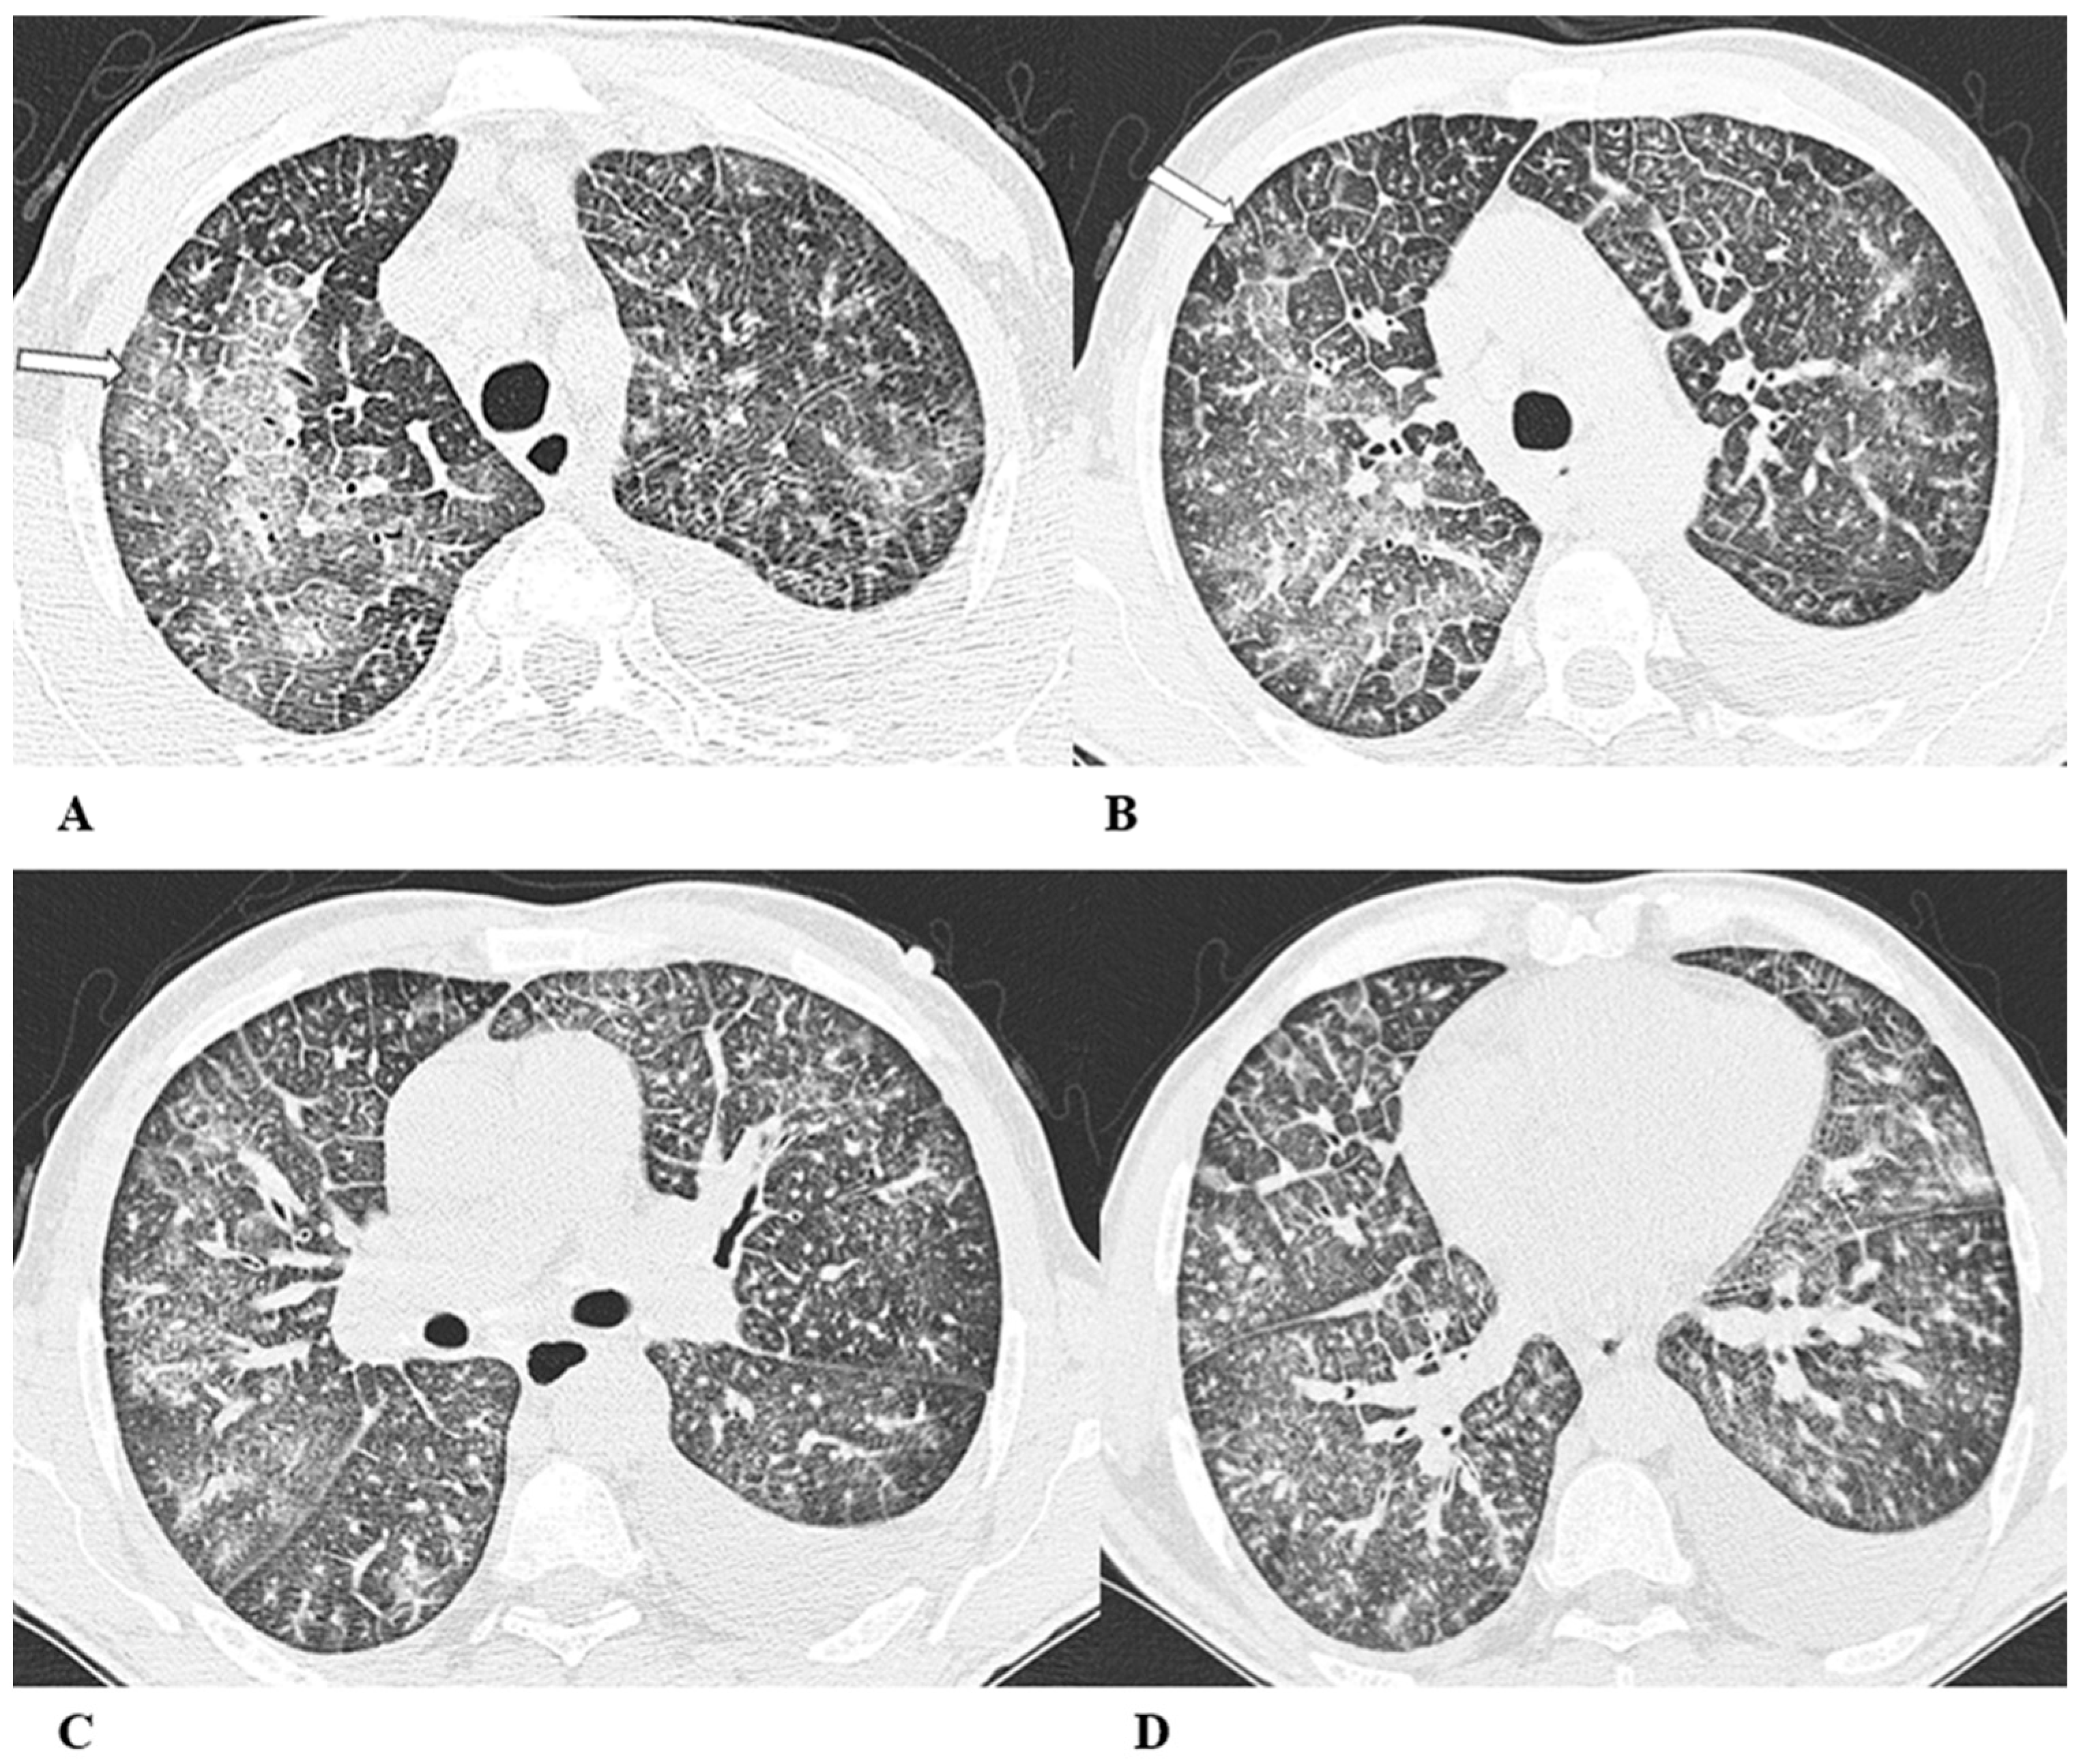

Figure 1.

Organizing pneumonia (OP). Organizing pneumonia is determined by the presence of granulation tissue buds in the alveoli, alveolar ducts and distal bronchioles. On HRCT, OP is characterized by diffuse and bilateral areas of consolidation and ground-glass opacities (GGOs), often migratory, with predominantly peripheral/subpleural and peribronchovascular distribution [9,12]. Other OP findings are the “reversed halo sign” (a focal area of GGO surrounded by a ring of denser air-space consolidation; if the surrounding ring is incomplete, it is mentioned as the “atoll sign” [16]) and, rarely, centrilobular nodules.

(A–D) A 64-year-old man with a diagnosis of small-cell lung cancer with adrenal and brain metastases, treated with nivolumab. Six months after beginning immunotherapy, the patient presented progressive dyspnea and dry cough. Chest auscultation revealed diffuse crackles associated with a moderately restrictive functional pattern. The blood count did not show significant leukocytosis but showed increased inflammatory indexes. The patient benefited from a temporary suspension of immunological therapy with steroid intake, but the subsequent relapse forced a radical change in therapeutic strategy.

Axial chest CT images (A–D) show bilateral confluent areas of GGOs and peripheral and peribronchovascular consolidative opacities.

The structural alteration of the right pulmonary hilum due to the presence of neoplastic tissue, with the infiltration of the ipsilateral main bronchus (A) and the “reversed halo sign” (white arrow (D)), are also visible.